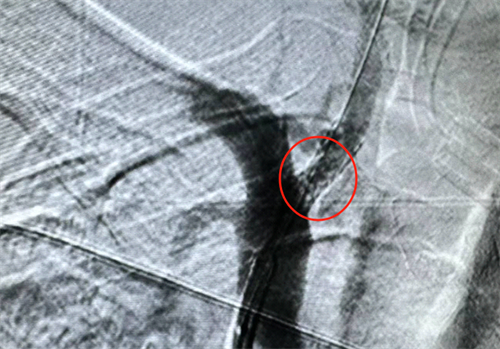

一名72岁的男性患者,因无明显诱因出现右侧肢体乏力到夹江县人民医院检查,医生结合辅助检查并行脑血管造影检查发现患者病症为椎动脉狭窄诱发的梗死。

神经外科医生考虑到患者为后循环供血系统病变,如不及时处理,患者极可能会出现头晕症状加重、四肢瘫痪,吞咽困难、意识障碍等严重神经功能障碍,增加患者痛苦及家庭负担,严重者可危及患者生命。经过术前准备,神经外科团队在介入导管室的精细配合下,以微创介入的手术方式成功为患者实施了椎动脉狭窄支架成形术,整个术程迅速且顺利,术后造影证实支架位置良好,打开完全,狭窄解除,血流通畅。

(手术前患者血管情况)

(患者术后椎动脉情况)